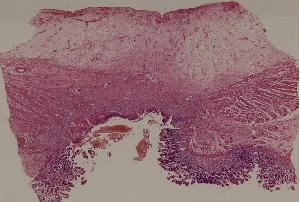

60.胃溃疡